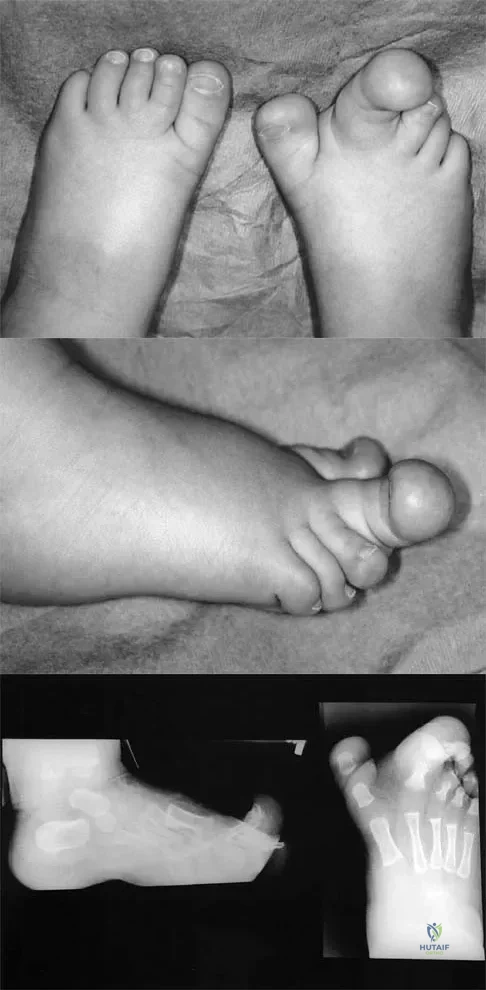

Figures 4a through 4c show the clinical photographs and radiographs of a 12-month-old boy who has progressive difficulty wearing shoes because of the length of the second toe, as well as width of the forefoot. Management should consist of

Explanation